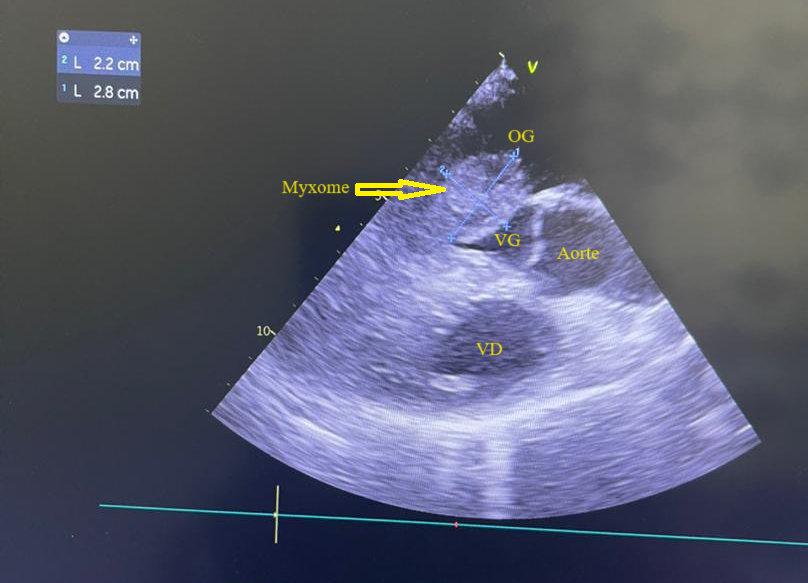

L’électrocardiogramme notait un rythme sinusal régulier avec une fréquence cardiaque à 83 bpm, des anomalies de la repolarisation en antéro septal à type d’ondes T biphasiques et en inférieur à type d’ondes T négatives asymétriques. La biologie était normale. L’échocardiographie (transthoracique et transœsophagienne) retrouvait les mêmes caractéristiques avec une masse appendue à la face atriale de la grande valve mitrale, obstruant partiellement l’orifice mitral et mesurant 49mm ×27 mm. Elle faisait protrusion dans le ventricule gauche en diastole (Figures 5 et 6). Cette masse était évocatrice d’un myxome de l’oreillette gauche. Le ventricule gauche n’était pas dilaté (DTDVG= 46mm), avec une fraction d’éjection systolique à 74% au Simpson biplan. Les pressions de remplissage du ventricule gauche étaient élevées. L’oreillette gauche était dilatée (VOG= 43mL/m²). Les cavités droites n’étaient pas dilatées. La fonction ventriculaire droite était normale (TAPSE= 24mm). On notait une hypertension pulmonaire avec PAPS =75mmHg, VmaxIT= 4,18 m/s. La veine cave inférieure était fine et compliante.

Figure 5 (a, b et c): Echocardiographie transthoracique en mode bi dimensionnel montrant un large myxome de l’oreillette gauche appendu à la face atriale de la grande valve mitrale faisant protrusion dans le ventricule gauche en diastole vu en incidence apicale 4 cavités (a et b) et 2 cavités avec doppler couleur notifiant une insuffisance mitrale (c) chez un patient de 57 ans. (Cas clinique n° 3). VG= ventricule gauche ; OG= oreillette gauche ; OD= oreillette droite ; VD= ventricule droit

Figure 6: Echocardiographie transoesophagienne en bi dimensionnelle, incidence 4 cavités vue bi-commissurale montrant un myxome appendu à la face atriale de la grande valve mitrale et faisant protrusion dans le ventricule gauche en diastole (Cas clinique n°3). VG= ventricule gauche ; OG= oreillette gauche.